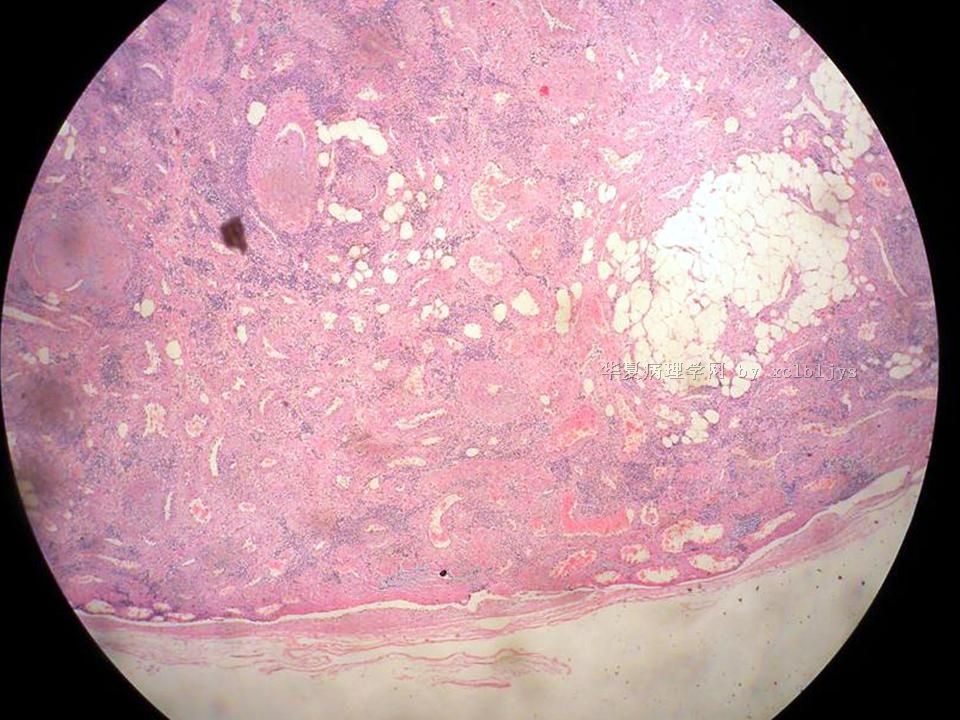

| 以下是引用xclbljys在2010-12-22 17:20:00的发言: 本例我们科室医生有两种意见:一种是炎性假瘤;第二种意见是炎性假瘤伴局限性Wegener肉芽肿。 依据是眼眶内肿块含有大量的动脉内膜炎改变,浸润的炎细胞有淋巴细胞、浆细胞、嗜中性粒细胞和嗜酸细胞等,如图16所示,炎细胞已经浸润动脉壁全层,应符合坏死性小动脉炎,但尚不能确定动脉壁弹力纤维层的破坏。 请各位老师点评! Wegener肉芽肿多发生在上呼吸道、肺、肾脏和皮肤等器官与组织。坏死性血管炎需证实有纤维素样坏死。小动脉炎多在皮肤病变比较明显。本例的小动脉炎或许是炎症引起的继发性改变。需要完善病史,查血免疫指标,看有没有系统性疾病。如果没有系统性疾病,还是考虑慢性炎症继发小血管炎。

血管炎是正常营养/供给血管的炎症性病变,而不是增生血管的炎症。血管炎往往有明显的临床相应症状,如皮疹。典型的Wegerner肉芽肿病有三联症(上呼吸道、肺、肾脏病变)。血管炎不仅是有炎症细胞,同时有血管壁的变性、坏死(纤维素样), 内皮细胞的变质和增生,炎症细胞浸润(包括中性粒细胞、淋巴细胞、组织细胞、嗜酸性细胞、巨细胞等)。不同类型的血管炎累及的血管大小、炎症细胞的类型、有无肉芽肿改变都不相同。血管炎的病因可以是过敏、自身免疫、胶原性疾病、感染等多种因素。